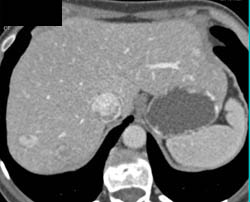

Cavernous Trnasformation of the Portal Vein With Portal Vein (PV) Occlusion